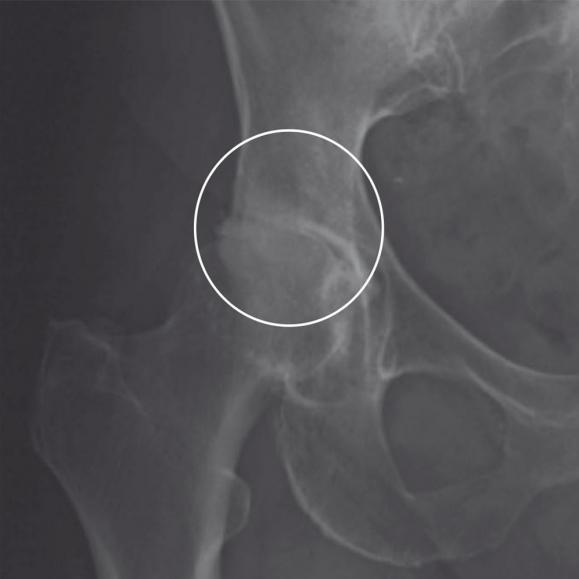

Entfernung des Hüftkopfes

Der erkrankte Hüftkopf wird vom Oberschenkelhals abgetrennt und entnommen.